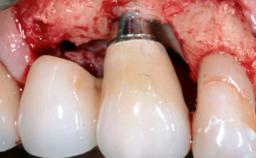

Resective Surgical Treatment of Peri-Implantitis Including Implantoplasty

In this case, Myroslav Solonko, Ignacio Sanz Sánchez and Mariano Sanz present a treatment that aims to eliminate exposed implant threads by modifying the implant surface, converting a moderately-rough surface into a smooth surface.

A 63-year-old male patient was referred to the post-graduate periodontal clinic of the Complutense University of Madrid for the treatment of peri-implantitis. According to the patient’s record, all his maxillary teeth had been extracted ten years previously due to severe periodontitis, and a full-mouth implant-supported restoration on eight implants was placed. No supportive periodontal therapy was provided apart from occasional check-ups by the restorative dentist.